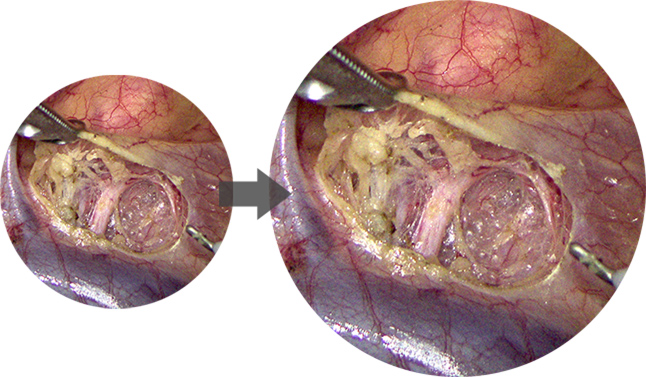

Wide Color Gamut

Restore the organs and tissues in real color, perfect identification of blood vessels, lymph nodes and nerves.